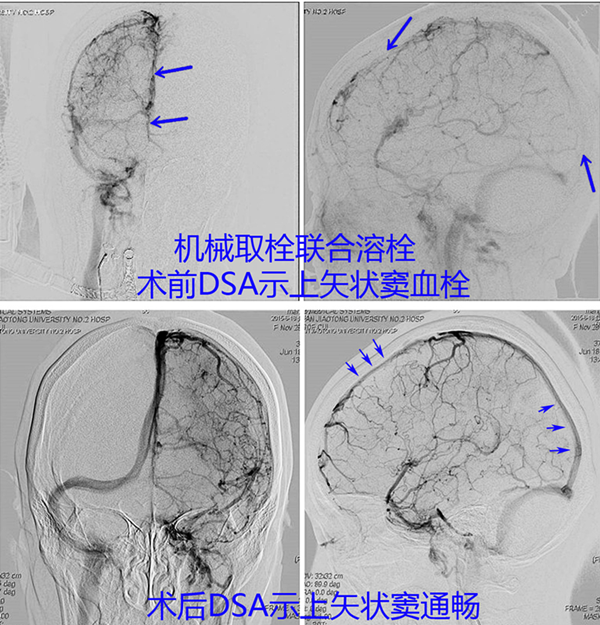

病例2、患者45岁,女性,因癫痫持续状态由外院转入,行DSA提示:上矢状窦血栓,予以机械取栓联合溶栓治疗。

图.1 机械取栓联合溶栓治疗前后